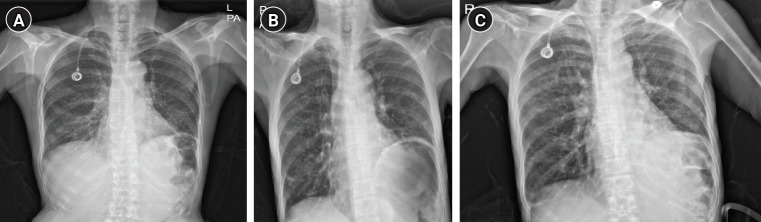

Case: A 63-year-old female patient underwent triple arthrodesis on her ankle under GA using an SGA (I-gel® size 3). After surgery, she suffered from nausea and abdominal bloating. A chest radiograph revealed that a large amount of air in her stomach had caused gastric distention, which resulted in left hemidiaphragm elevation and atelectasis.

Conclusions: This case illustrates that the use of I-gel® in prolonged surgeries may result in malposition of the SGA and gastric insufflation and atelectasis.